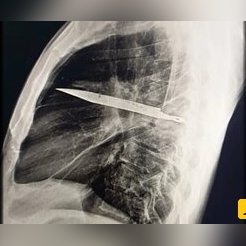

عکس| کشف شی عجیب در قفسه سینه یک مرد بعد از 8 سال؛ چاقویی که در بدن ریشه کرده